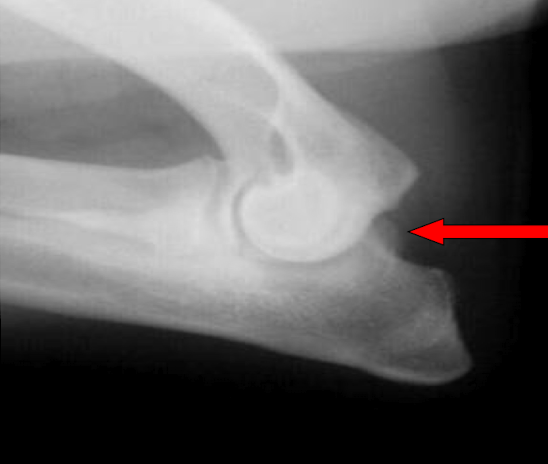

What is the arrow pointing to?

intra-capsular swelling

large osteophyte on the anconeal process (earliest change seen in DJD)